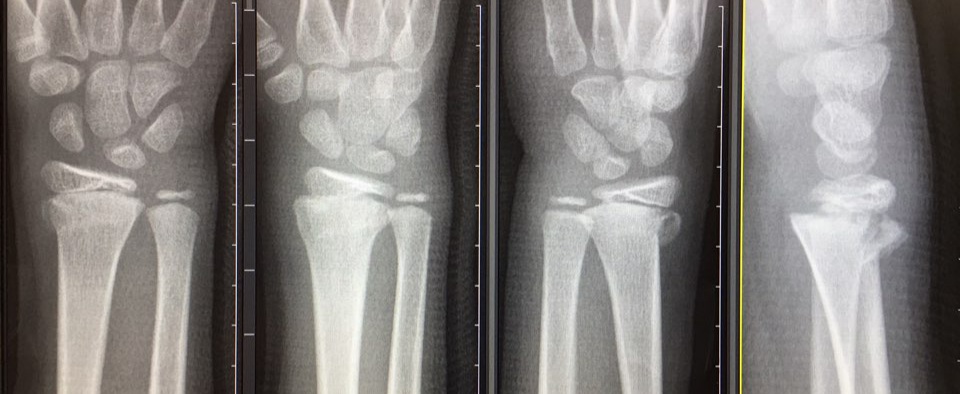

병원으로 와서 엑스레이를 찍었더니, 우측 요골(radius)의 원위부 골절인데, 성장기에 닫히지 않은 성장판(epiphyseal plate)도 침범한 상태였다.

다시 찍어본 엑스레이에서 성장판 원위의 골단(epiphysis) 위치가 너무 밀려있지 않아, 다행히 수술은 하지 않고, 손목을 당기고 움직여 조각난 뼈를 맞추기(reduction)로 결정됐다

reduction은 대학 동기 교수님이 직접 해줬는데, 정말 깔끔하게 잘 맞춰졌다. 이 포스트를 빌어서 감사함을 전하고 싶다.